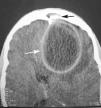

Figura 1.

Paciente de 19 años de edad sin antecedentes de interés. Presenta cuadro de malestar general, astenia y febrícula de dos meses de evolución al que se añade en los últimos días cefalea frontal y tendencia al sueño. Se realiza tomografía axial computarizada (TAC) craneal con contraste observando una lesión hipodensa de 6 x 5 cm con captación periférica en anillo (fig. 1), sugestiva de absceso cerebral (flecha blanca) junto con la existencia de sinusitis frontal y rotura de la tabla posterior del seno frontal (flecha negra). Se procede a drenaje quirúrgico tras el cual el paciente ingresa en la Unidad de Cuidados Intensivos. Recibe tratamiento antibiótico empírico aislándose posteriormente un Streptococcus pyogenes sensible al tratamiento instaurado. Evoluciona favorablemente, siendo dado de alta en 48 horas sin secuelas.